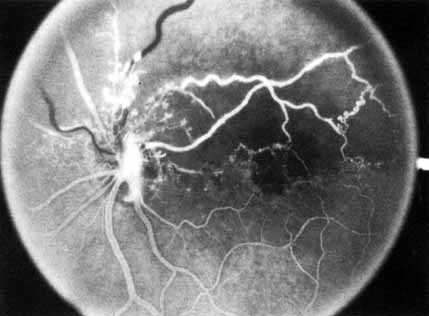

The prognosis for ischemic central retinal vein occlusion is generally poor because of decreased visual acuity and neovascularization. Visual loss occurs because of macular edema, capillary nonperfusion, overlying hemorrhage (either retinal or vitreal), or a combination of all these. Retinal edema usually gradually subsides except in the macula, where it may persist for many months or years. Macular holes or cysts may form.83,84 Pigment clumping or fine pigment stippling and pigment atrophy are not uncommon, and persistent macular hemorrhage, even years after the occlusion, has been noted.83 Hard exudates often form an irregular circinate configuration around the macula and become more prominent months later. Occasionally an epiretinal membrane may form. In the chronic phase, most hemorrhages gradually disappear over many months; however, scattered, flame-shaped hemorrhages and dot hemorrhages, particularly in the periphery, may be seen for years. Cotton-wool patches and microaneurysms likewise tend to disappear after several months, although in some cases the latter may persist. The venous tree becomes less tortuous and dilated. Prominent venous loops, which are collateral communications, may be observed on the surface of the disc (Fig. 6).85 These loops develop within 3 to 14 months after occlusion from the existing retinal vasculature and are collateral vessels between the obstructed disc capillaries and the unobstructed choroidal or pial capillaries.323 These retinochoroidal collateral veins, if they develop, may protect against anterior segment neovascularization,328 but may not be associated with a better visual prognosis.105 Collaterals between the central retinal vein within the globe and the patent central retinal vein behind the occlusion have not been observed.86 The extent and speed of retinal recovery probably depends to some degree on how quickly collateral vessels form, how rapidly recanalization occurs, and how adequately these compensatory mechanisms restore normal outflow. However, the exact nature and course of the collateral vessels are disputed. Anastomotic channels may develop within the retinal vasculature if pressure differentials develop between its major venous trunks. Changes in the retinal arterioles include both segmental and generalized narrowing as well as sclerosis, which is evidenced by both sheathing and widening of the light reflex. Sheathing of the veins is also common. The disc may appear nearly normal except for sheathing of the vessels in and around the papilla, and some blurring of the margins may persist. Sometimes optic atrophy is present. The fluorescein angiographic appearance varies greatly, depending on the extent of recovery. All the findings in the acute phase, consisting of venous and capillary engorgement, microaneurysms, staining of the veins, patchy extravascular fluorescence, and capillary nonperfusion, may persist indefinitely. In most instances, these findings eventually diminish so that few significant features are present on the angiogram; collateral vessels, if present, may be the only pathognomonic feature. The most serious complication of central retinal vein occlusion is neovascularization (Table 2). Neovascularization elsewhere (NVE) occurs less frequently than neovascularization of the iris (NVI), and usually only in ischemic occlusions.66 The low incidence of retinal surface neovascularization in ischemic central retinal vein occlusion is thought to be due to the destruction of endothelial cells, which provide the source for endothelial proliferation and neovascularization.87

The terms hemicentral, hemiretinal, and hemispheric retinal vein occlusion refer to eyes in which approximately half the venous outflow from the

retina, either the superior or the inferior, has been occluded. In approximately 20% of

eyes, the branch retinal veins draining the superior

and inferior halves of the retina enter the lamina cribrosa separately

before joining to form a single central retinal vein.175 Hemicentral retinal vein occlusion is an occlusion of one of these dual

trunks of the central retinal vein within the nerve.176,177 Hemispheric retinal vein occlusion is an occlusion involving the venous

drainage from approximately half of the retina, either the superior

or the inferior retina (Fig. 7; see Fig. 11).75,178 This has also been referred to as a hemiretinal occlusion.362,363 In some eyes, the occlusion occurs in one of the dual trunks of the central

retinal vein in which such a pattern exists (and then would

qualify as a hemicentral retinal vein occlusion); the term hemispheric retinal vein occlusion actually includes the term hemicentral retinal vein occlusion.

In some eyes, the nasal retina is not drained by a separate vein, but by a branch of either the superior or the inferior temporal vein.179 It is the occlusion of one of these veins draining both the nasal retina and the superior or inferior retina near the optic disc that accounts for the majority of hemispheric retinal vein occlusions.75 In some eyes, however, it is impossible to determine the site of occlusion even with a good-quality fluorescein angiogram,75 and that is why we prefer the term hemispheric to describe this type of occlusion. The retinal area involved, appearance, clinical course, and complications from neovascularization are similar for both entities (see Table 2). The treatment and classification are similar to that of branch retinal vein occlusion. The Eye Disease Case-Control Study reported the risk factors for a hemispheric or hemiretinal vein occlusion in a prospective study at five eye care centers.362 The three factors that were significantly associated with this type of occlusion compared to control were systemic hypertension, diabetes mellitus, and glaucoma. A reduction in risk with moderate alcohol consumption was noted, but it was not statistically significant, possibly because of the small number of cases (79) in this series.362 The study felt that there were more similarities than dissimilarities in the risk factor profiles for central retinal vein occlusion, branch retinal vein occlusion, and hemispheric or hemiretinal vein occlusion.362,363 We have seen one patient in whom a superotemporal branch retinal vein occlusion developed in the same eye with an inferior hemispheric retinal vein occlusion, producing the appearance of a three-quarter retinal vein occlusion. |